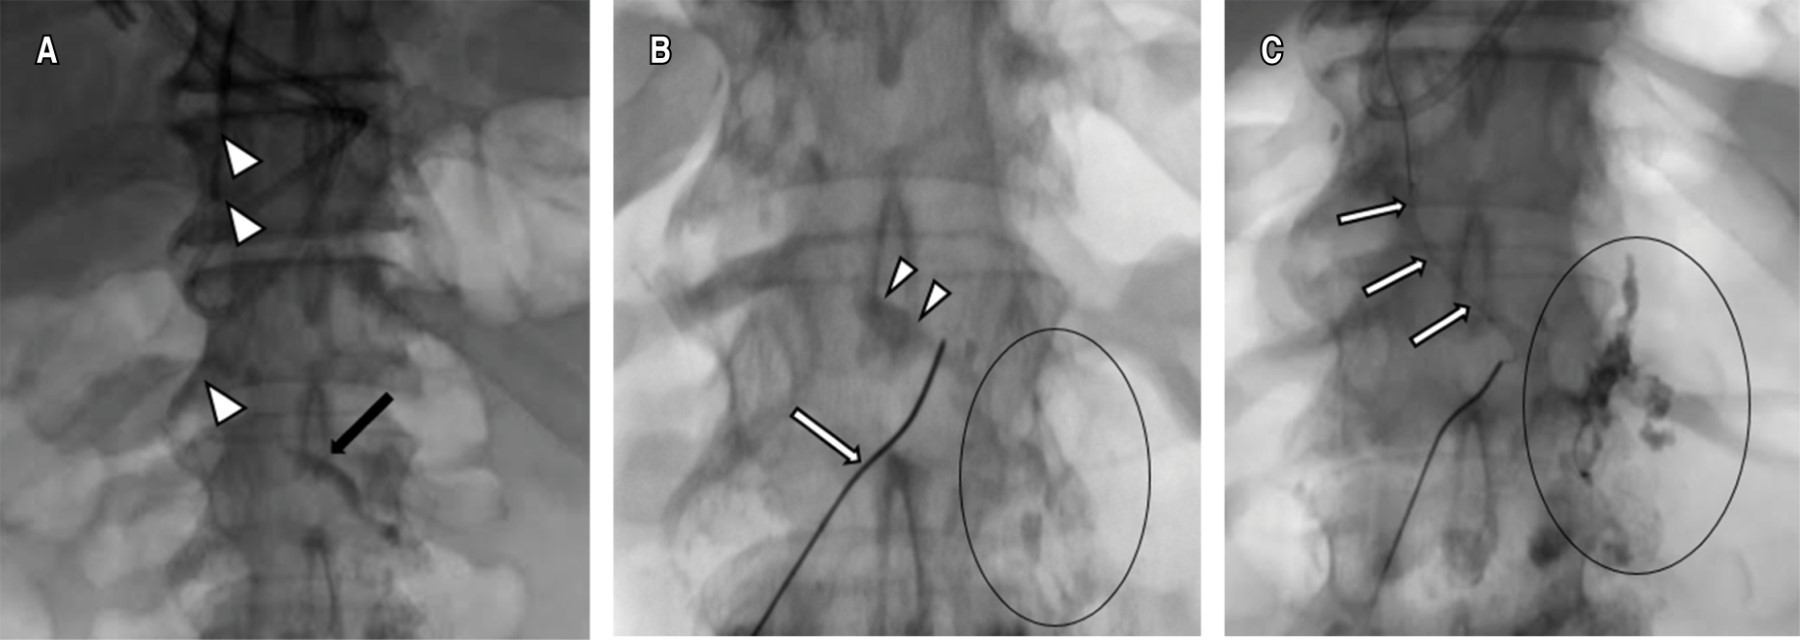

Once the chyle cistern was opacified, a disruption of the thoracic duct and contrast leakage into the left pleural cavity was visualized, under fluroscopic control the thoracic duct was catheterized using a 22 G Chiba needle by percutaneous abdominal approach in the epigastric area and with a slightly cranial angulation. Once accessed, a 0.014-inch guidewire was introduced into the thoracic duct and the needle was exchanged for a microcatheter, which was placed as close as possible to the site of the thoracic duct lesion, ideally joining the point of extravasation (Figure 2). Subsequently, it was embolized with microcoils of 2 and 3 mm in diameter proximal to the leak and the embolization was completed with cyanoacrylate. Control ductography showed the resolution of the leak (Figure 3).